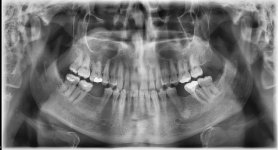

أشكو من ألم في الجهة اليسرى من الفك العلوي ينحصر في منطقة جناح الأنف الى منتصف الخد. طبيب الأسنان لم يستطع تشخيص الألم ووصف لي مضاد التهاب كلاموكس 1 ملغ لمدة 3 ايام وقال ان لم يذهب الألم فهو يشك في الضرس العلوي الذي تم حشوه مؤخراً.

أيضاً لدي الضرس السٌفلي من نفس الجهة قام الطبيب بحشوه منذ فترة وسحب عصبه ولكن الأن اشعر بألم خفيف عند الضغط او الطرق عليه.

تشخيص طبيبك

لم يستطع وقال انه يشك بالضرس في الفك العلوي الذي تم حشوه مؤخراً وصرف لي مضاد التهاب لمدة 3 ايام وقال من بعدها ان لم يذهب الألم راجعه.

قد يكون بالفعل المشكلة في الضرس الذي تم حشوه ، لذا لم يختفي الألم يجب فحص الضرس مرة أخرى. من الضروري عمل فحص للتوصل لتشخيص صحيح . نتمنى لكم السلامة والعافية.